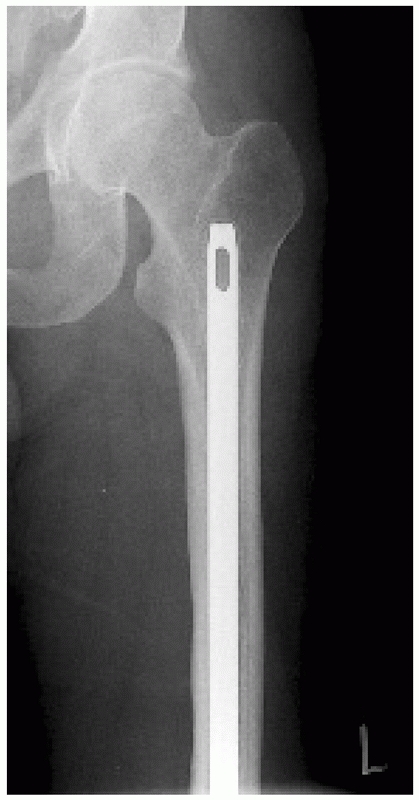

![]() |

FIGURE 50-1

A comminuted, segmental, open femoral shaft fracture with bone loss that occurred after a motorcycle crash. Despite the complexity of the injury, current nail designs and nailing techniques make stabilization of this injury possible. |